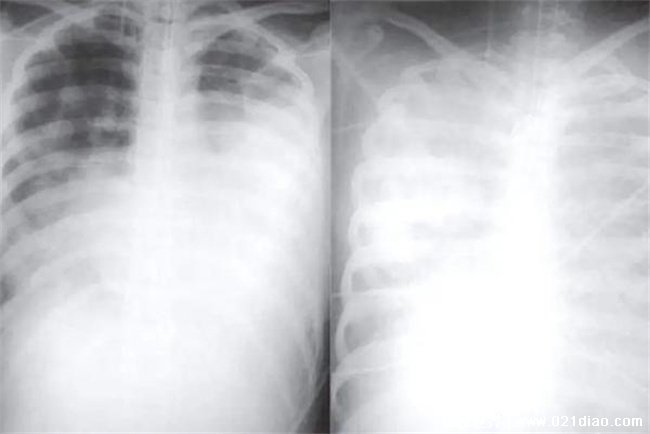

专家回应,现在出现的所谓白肺和武汉当时的原始毒株以及疫苗接种没有关系,现如今比较流行的优势毒株仍然是奥密克戎毒株。专家还表示白肺是属于肺部影像学表现的一种口语化的描述,在正常的情况之下,肺部是由肺泡组成,肺泡里面都是充满着空气的,所以在进行CT或者是X光线检查的过程当中表现出黑色的影像。当肺泡当中出现了炎症或者是感染以及有渗出液或者是炎性细胞的时候,在拍摄CT或者是X线的时候,就出现了白色区域,俗称的白肺。